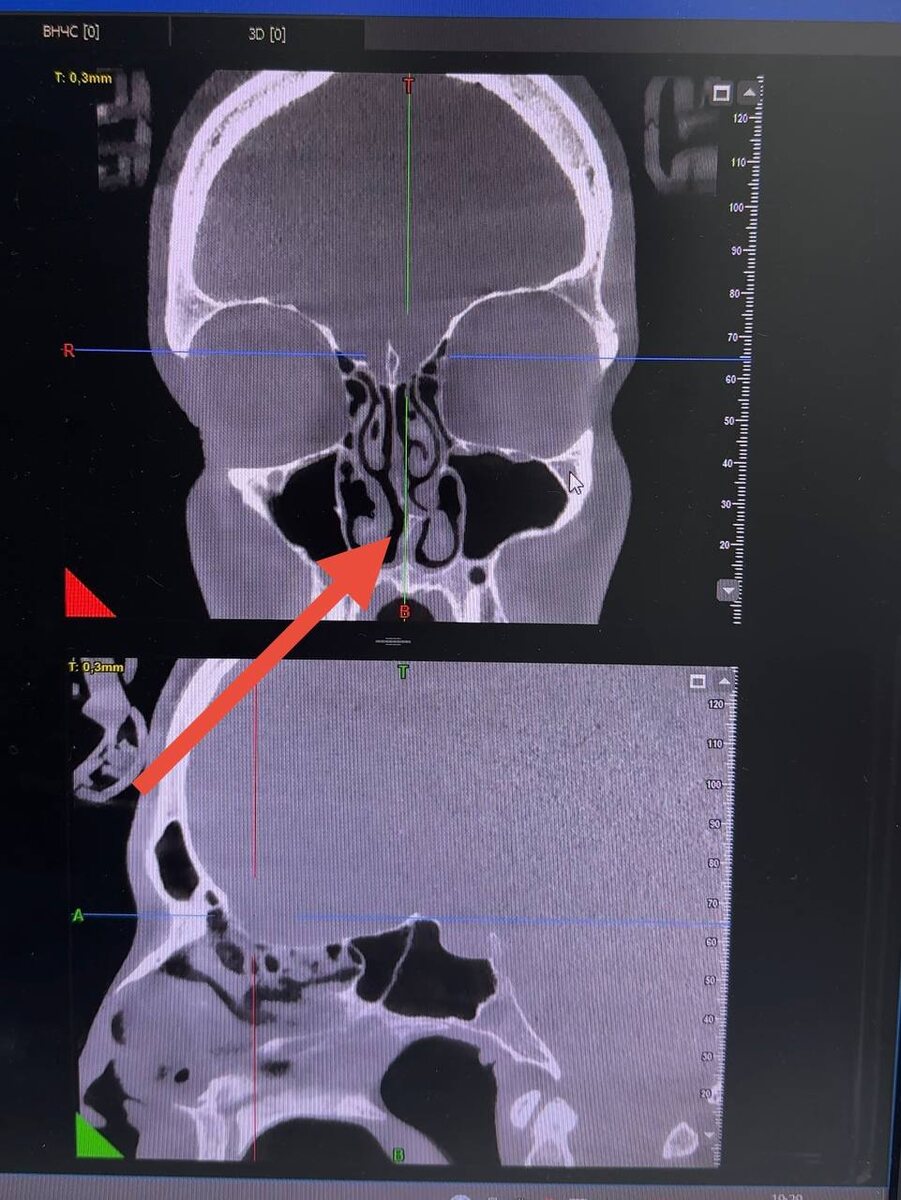

Ps: на фото ⤵️кт пазух носа человека с искривлением носовой перегородки и хроническим ринитом. Отметила стрелочкой.

Что покажет компьютерная томография, если нос не дышит

▪️насколько искривлена носовая перегородка и мешает ли это носовому дыханию